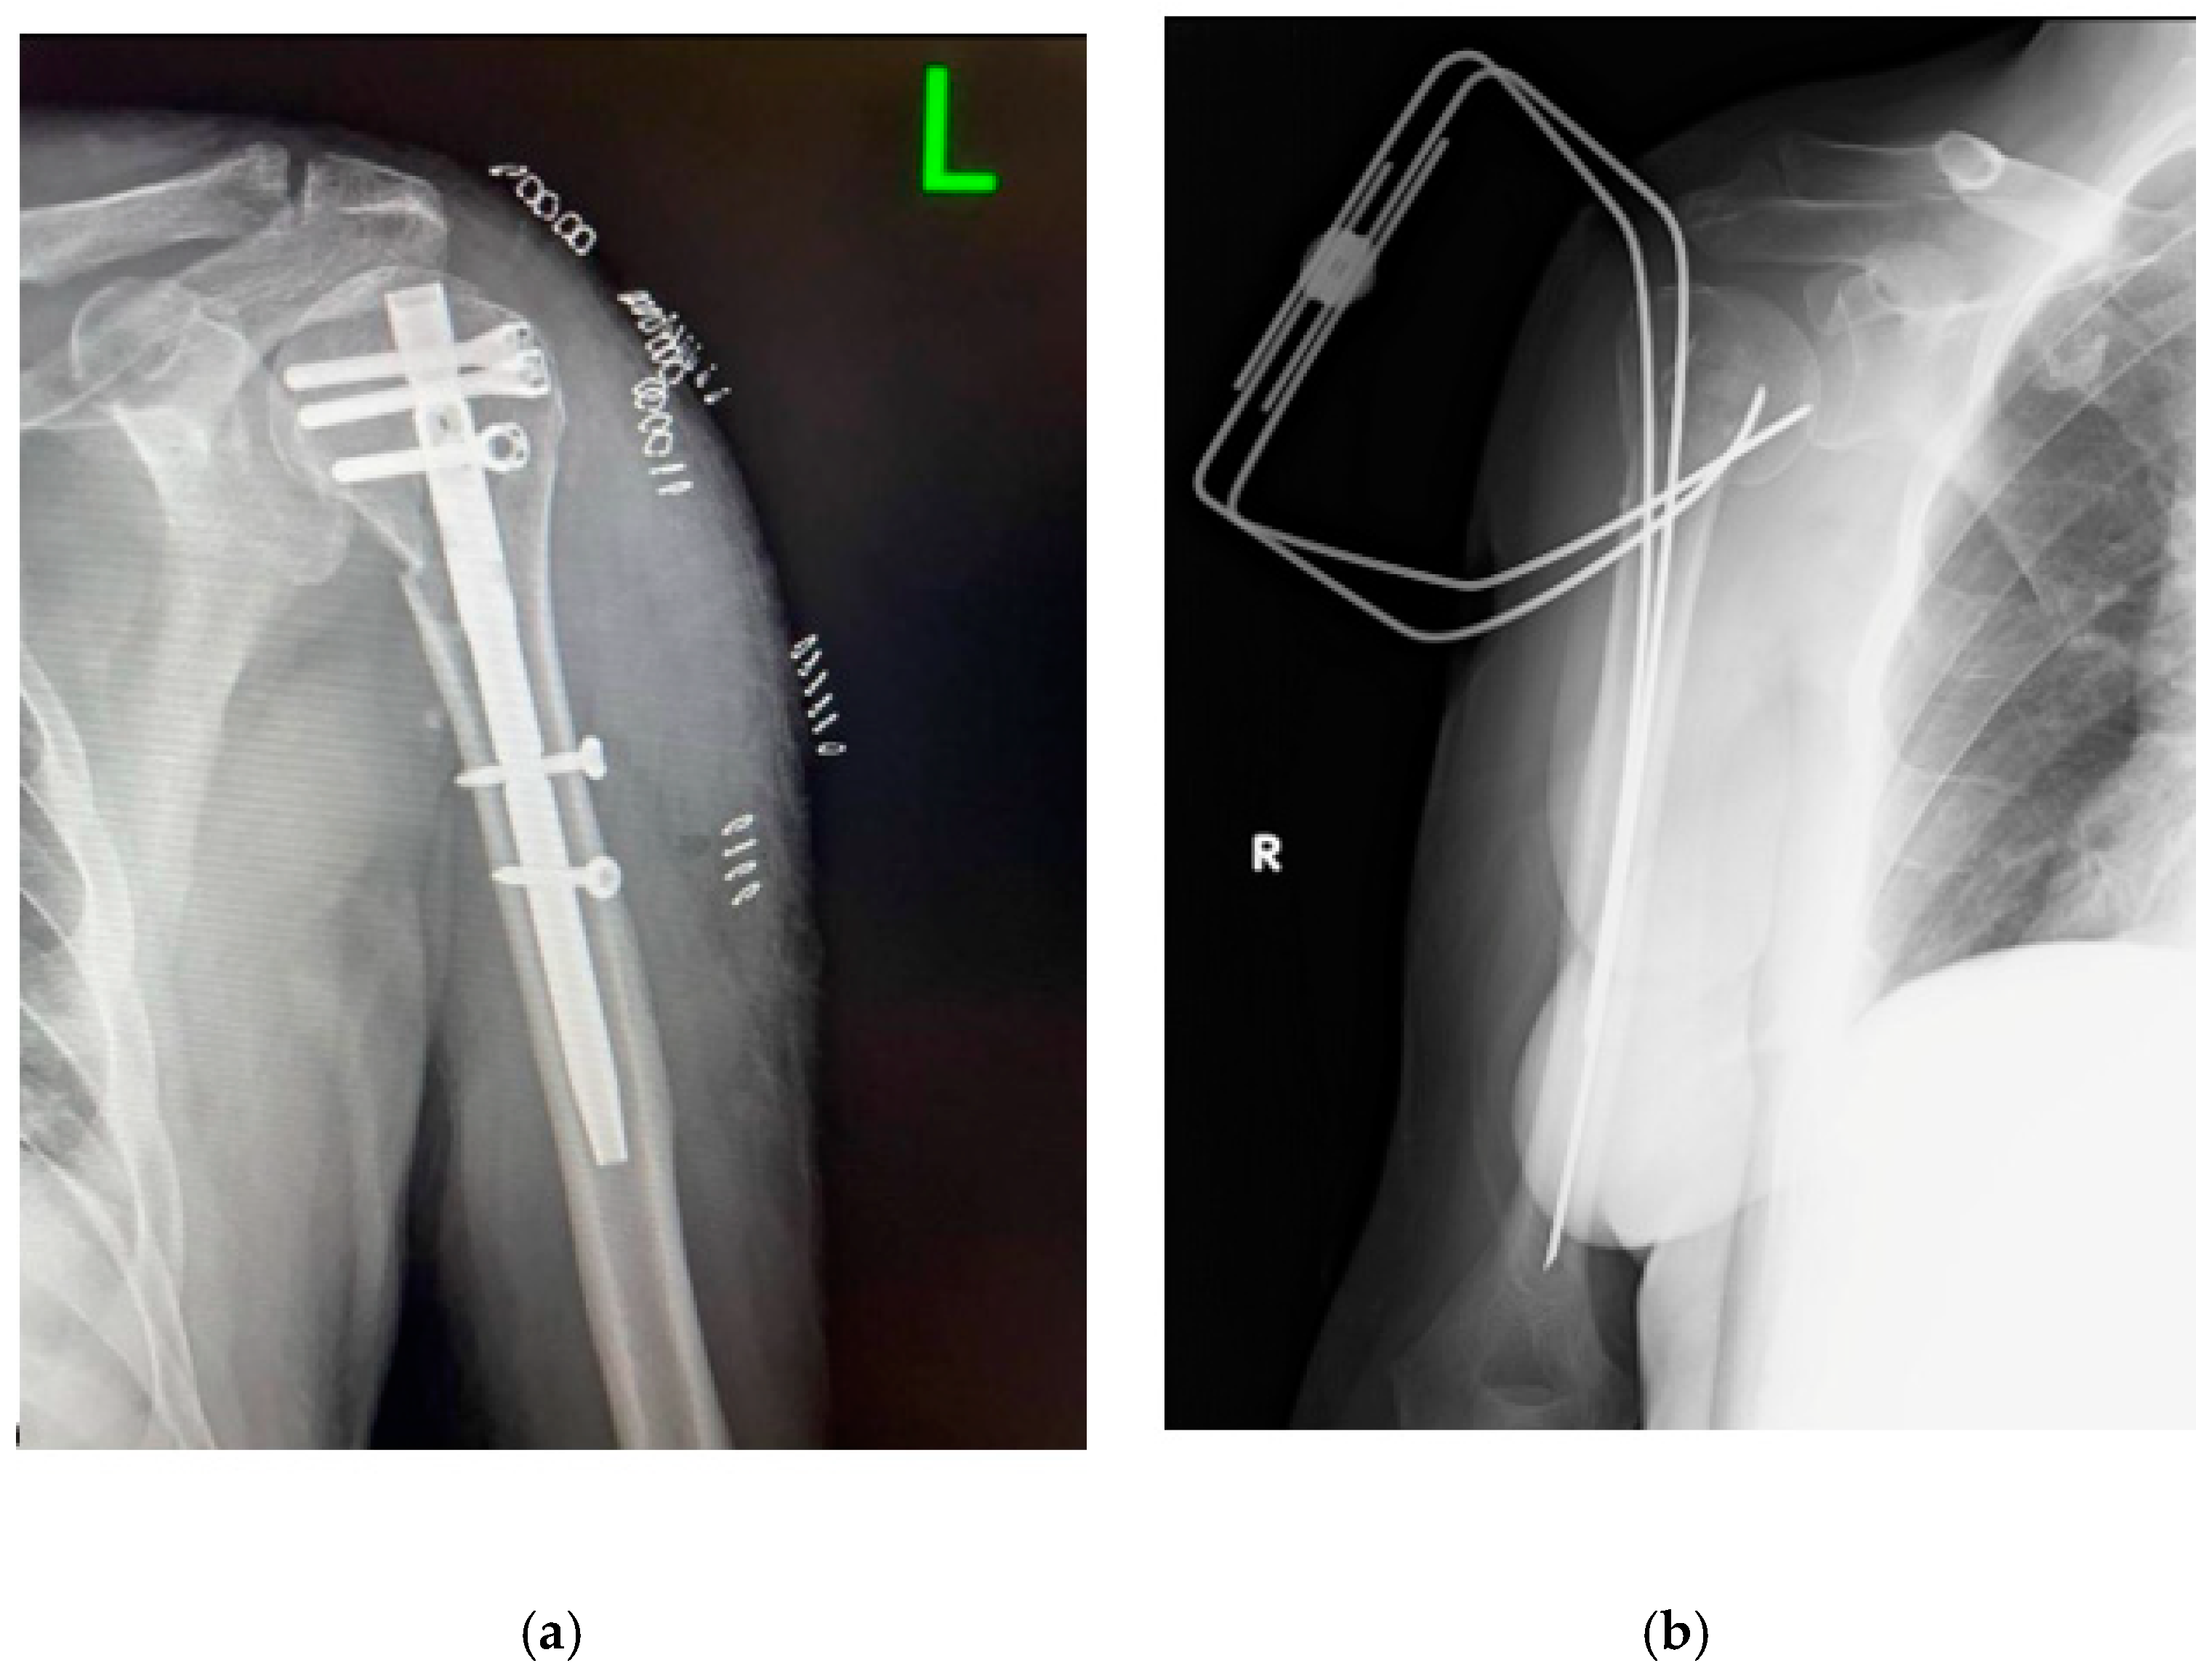

Treatment of Fractures of the Humeral Surgical Neck: MIROS Versus Intramedullary Nailing—A Retrospective Study

Palco, M.; Giuca, G.; Fenga, D.; Sanzarello, I.; Nanni, M.; Leonetti, D. Treatment of Fractures of the Humeral Surgical Neck: MIROS Versus Intramedullary Nailing—A Retrospective Study. Complications 2024, 1, 83-90. https://doi.org/10.3390/complications1030013